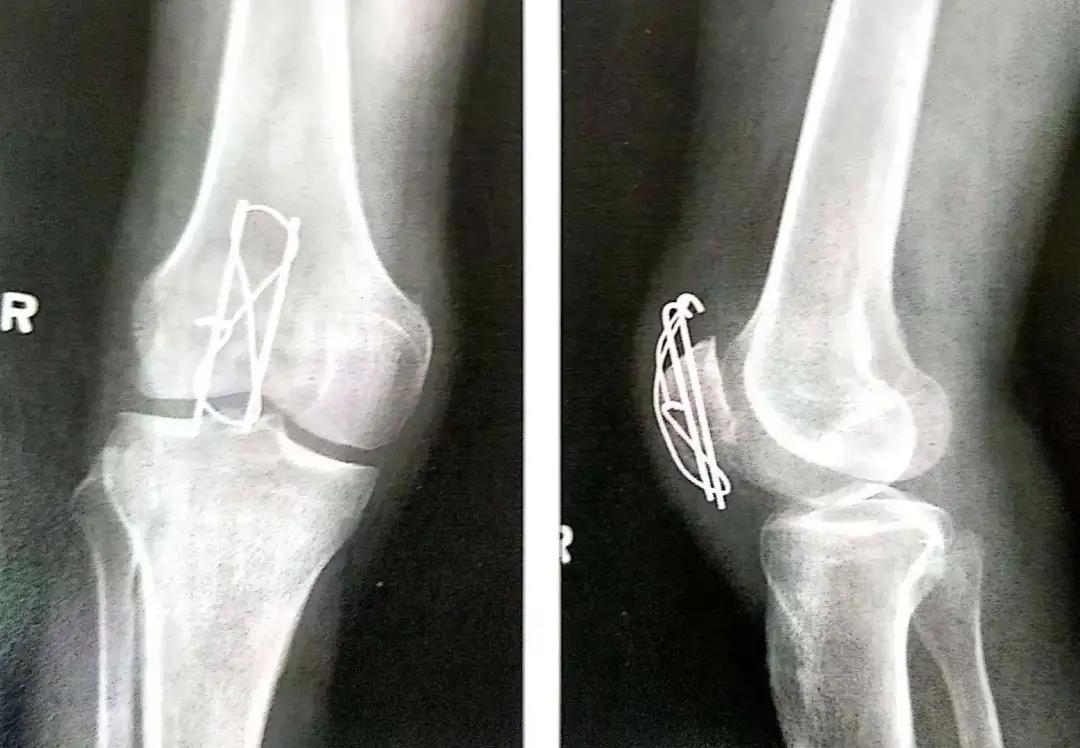

髌骨骨折手术技巧!

- 外科手术的目的是为了获得解剖复位,并在骨折愈合前以内固定的方式来维持复位状态,恢复髌骨骨折后的伸肌装置。

- 前张力带可将股四头肌产生的牵拉力转化为对关节面的压力。

- 克氏针或螺丝钉应在髌骨前皮质面下大约5mm打入,在骨质内冠状面和矢状面上相互平行。

- 在穿过骨折线之前,可用术中透视(正位和侧位)直视下或将手指伸到髌骨下触摸的方式来确保骨折已复位。

- 钢丝的两端在髌骨前面呈8字形交叉。张力带也可打成非交叉的方式。

- 在直视,触摸或同时借助于术中透视的方式下确保髌骨的关节面达到充分复位,这点非常重要。

- 8字形钢丝的内外两边要交替拧紧以使横过骨折端的张力均衡。

- 两平行克氏针的末端剪断后在张力环上翻转180°,上下两端埋入骨内以防止其移位。

- 在关闭伤口前用术中透视或X线评估骨折复位和内置物的位置情况。